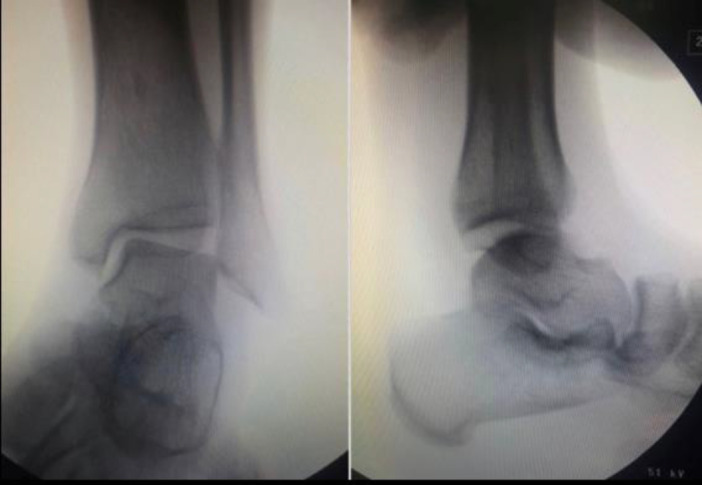

Abstract Image